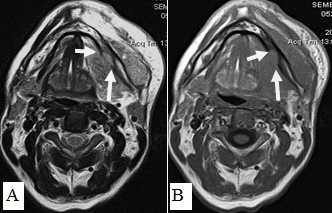

Сложно было с помощью МРТ визуализировать опухоли любых размеров с поверхностным распространением, не выходящие за пределы слизистой оболочки. Опухоли малых размеров (Т1 стадия) в 2 наблюдениях были однородны, не имели центральной зоны некроза и сливались с мышцами. С увеличением размера опухолевого узла отмечалась неоднородность структуры. В наших исследованиях удалось выявить небольшие опухоли Т1 и Т2 стадий, локализованные в области языка и дна полости рта. В 9 наблюдениях опухоли Т2 стадии, не накапливающие контраст при МСКТ исследовании, хорошо визуализировались при МРТ в режимах Т2-ВИ, STIR, проявляясь сигналом высокой интенсивности. Можно было четко видеть границы опухоли и оценить ее размеры (рис. 9,10).

Не возникало сложностей в выявлении опухолевых узлов Т3, Т4 стадий, имевших все отмеченные выше признаки в различных сочетаниях в 36 исследованиях (рис. 11). Из 50 обследованных с помощью МСКТ и МРТ пациентов у 26 (52,0%) были выявлены метастазы в лимфатических узлах шеи. Поражались преимущественно лимфатические узлы I-II уровня. Признаками метастаза плоскоклеточного рака в лимфатических узлах были: увеличение размера лимфатического узла более 1,0 см, изменение формы лимфатического узла с бобовидной на округлую, структурные нарушения в узле, нечеткость наружных контуров узла, уплотнение окружающей жировой ткани на КТ или изменение сигнала на МРТ.

Рис. 10. А. Пациент Е., 52 года. МРТ полости рта, ротоглотки в аксиальной проекции, Т1-ВИ. Опухоль языка небольших размеров, границы визуализируются с трудом за счет перифокального отека (стрелки); В. Тот же пациент. МРТ в аксиальной проекции, Т2 с подавлением сигнала от жировой ткани. Визуализируются границы опухолевого узла, размеры опухоли языка четко определяются (стрелки)

Большинство пораженных метастазами лимфатических узлов имели размеры более 1,0 см, округлую форму (рис. 12). Внутривенное контрастирование при оценке изменений в лимфатическом узле являлось обязательным условием для уточнения внутренней структуры и выявления зон некроза. В результате гипоксии и распада ткани формируется центральная зона некроза, не накапливающая контрастный препарат при внутривенном болюсном усилении. При этом отмечается повышение плотности в периферических отделах лимфатического узла (рис. 13).